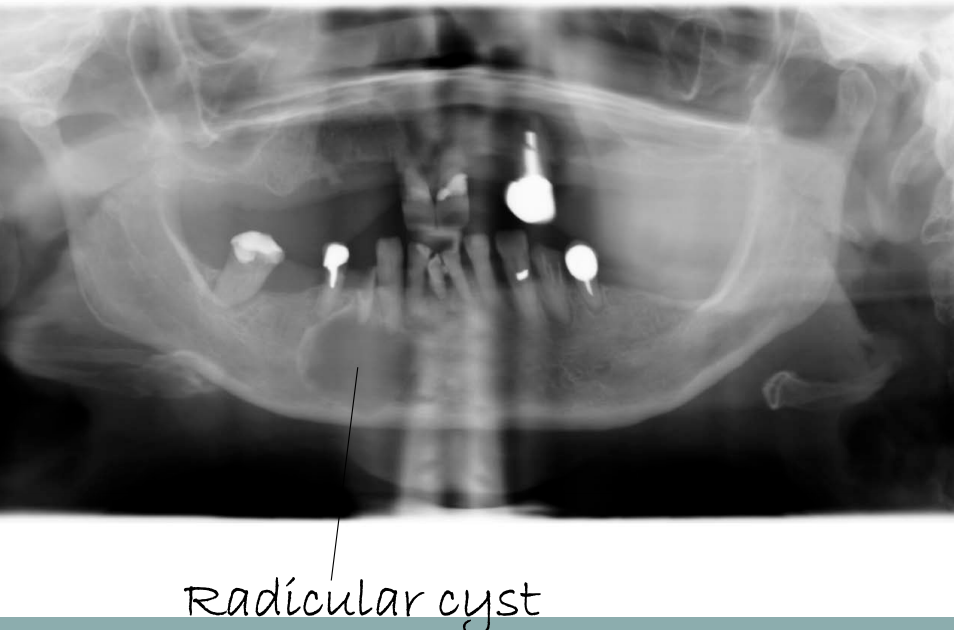

Radicular cyst